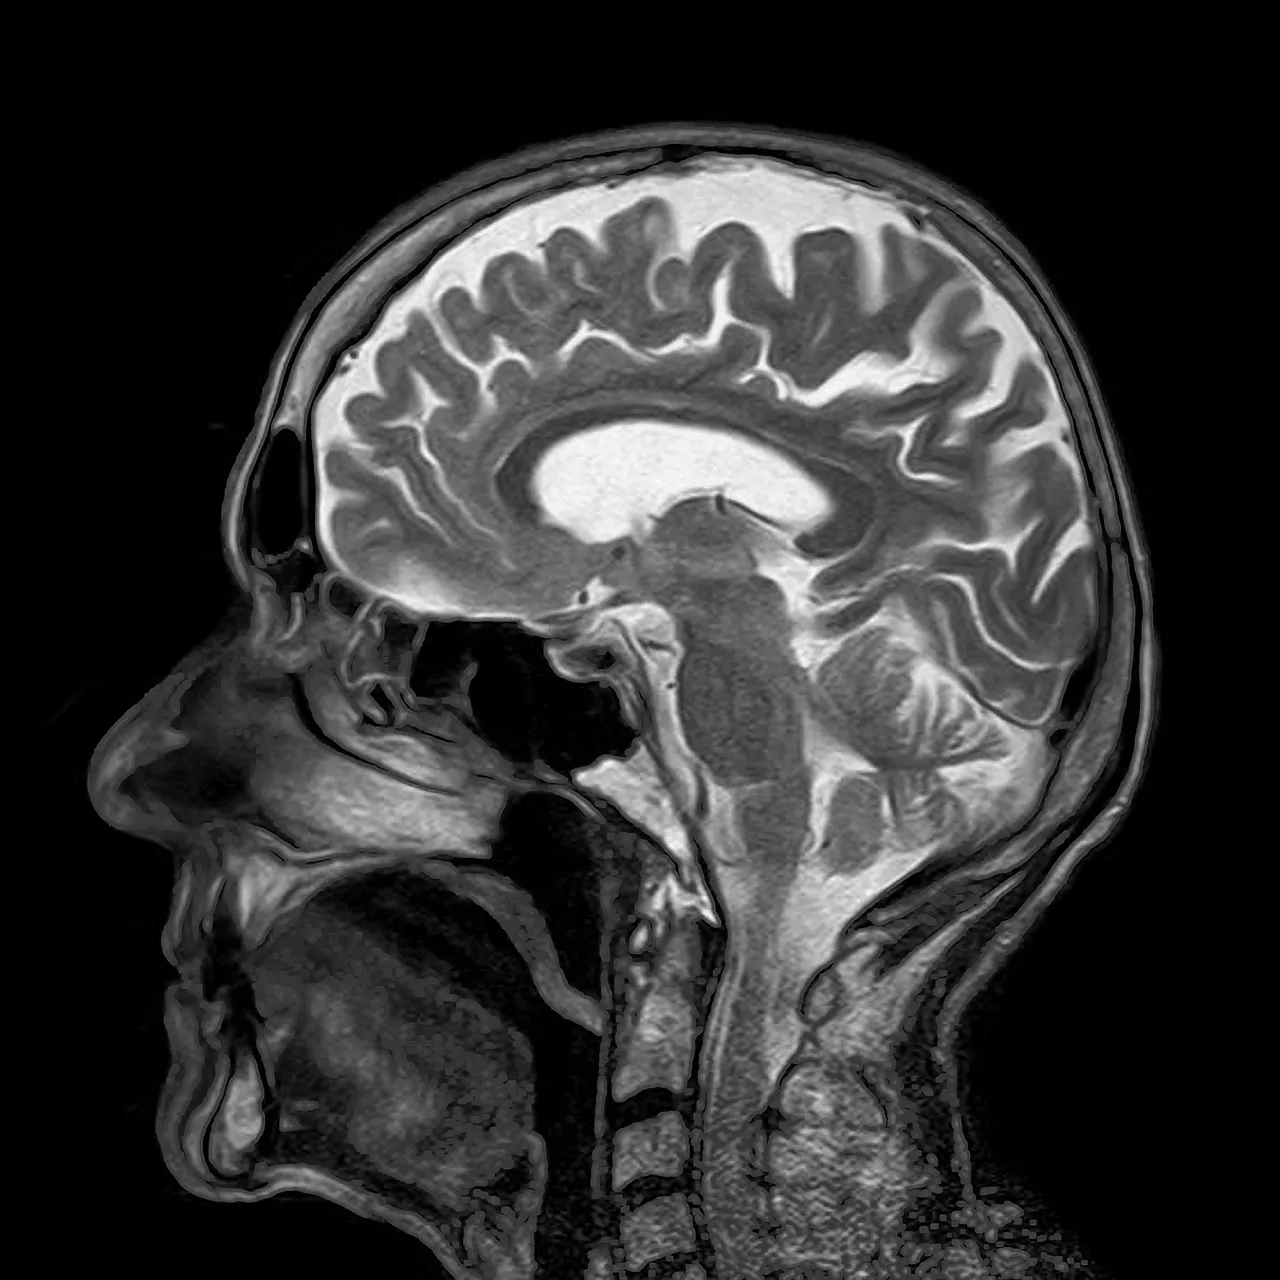

MRI - CT Scan und Co - Sinn oder Unsinn?

In einem grossen Artikel der neuenLuzerner Zeitung vom 14. Juni 2015stand ein Interview mit Dr.med. Josef Brandenberg (Orthopädischer Chirurg, Luzern) betreffend Sinn oder Unsinn von speziellen diagnostischen Abklärungen wie MRI, CT-Scan und Kontrastmitteluntersuchungen.

Wie auch Dr. Brandenberg feststellt, möchten Patienten genaue Abklärungen haben und immer das Neueste vom Neuesten ausprobieren. Wenn wir einen Patienten mit Rückenproblemen in der Physiotherapie haben, möchte der Patient in 90% der Fälle eine genaue Abklärung haben, was nun das Problem ist. Das grösste Problem aber ist, dass man mittels MRI, CT-Scan und Co.IMMER etwas findet.

Diese Untersuchungen zeigen jede kleine anatomische Abweichung, die Frage ist aber ob dies nun wirklich die Ursache des Problems ist?

In einer Studie von Prof. Peter O'Sullivan kam hervor, dass bei schmerzfreien Patienten im MRI Untersuch 91% der untersuchten Abnutzungserscheinungen aufzeigten, 56% hatten Bandscheiben Änderungen, 32% hatten eine Bandscheiben Protrusion (Vorwölbung der Bandscheibe) und 38% der Untersuchten hatten Risse in den Bandscheiben- Lammellen wo durch eine Diskus hernie entstehen kann. Ausserdem traf er Teilnehmer der Studie an, welche gar keine Schmerzen haben.

Brauche ich dazu ein MRI? Ich würde sagen in 80% der Fälle nicht! Weil wie bereits erwähnt, die Behandlung sich eigentlich nicht gross unterscheidet oder man mittels fundiertem Untersuch bereits viel ausfindig machen kann.